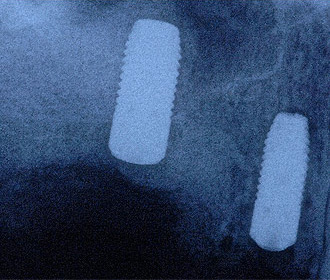

インプラント治療例

外傷による上顎左右11抜歯後即時インプラント+インビザライン矯正

インプラント治療時にはチタンメッシュ+人工骨による大掛かりな骨移植を行っている。

矯正治療、骨移植を伴うインプラント治療、セラミック・クラウン等による機能的、審美的治療

矯正治療、骨移植を伴うインプラント治療、セラミック・クラウン等による機能的、審美的治療

術前